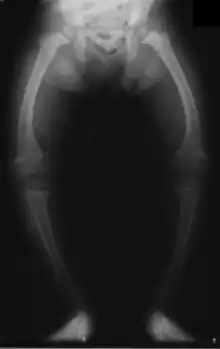

Les déformations osseuses prédominent aux membres inférieurs (aggravées par la station debout et la marche), en restant plus discrètes aux membres supérieurs. L'aspect le plus fréquent est le genu varum (jambes arquées en parenthèses) ; plus rare est la déformation inverse ou genu valgum (jambes arquées en X). La crête du tibia peut faire saillie « en lame de sabre ». Ces déformations indiquent un rachitisme sévère. Plus tardivement, une coxa vara (déplacement de la tête du fémur) peut apparaitre avec une « démarche en canard ».

Ces déformations retentissent sur le bassin osseux qui s'aplatit ou se rétrécit. Chez les filles, c'est une future source éventuelle de dystocie osseuse (accouchement difficile par bassin étroit), cause historique importante de décès maternel lors de l'accouchement.

La radiologie confirme le diagnostic, et il est inutile de les multiplier. Le défaut de minéralisation des os longs s'observe particulièrement sur les radiographies de face d'un poignet et des genoux : retard ou irrégularités des points d'ossifications attendus pour l'âge (maturation squelettique), lignes métaphysaires irrégulières donnant un aspect « en toit de pagode », la corticale de la diaphyse est amincie, la densité osseuse est diminuée donnant un aspect vermoulu. Les os longs s'incurvent.